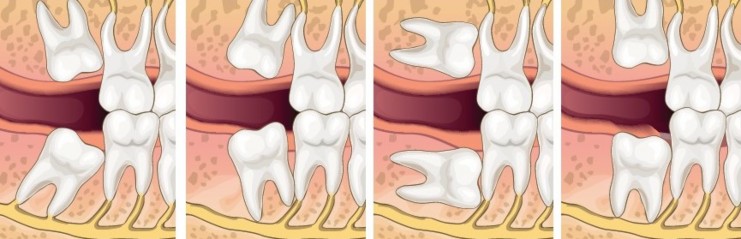

A wisdom tooth may get stuck or develop at an angle if there is not enough space to come through usually, we call this an impacted wisdom tooth.

If left untreated, this can affect your overall oral health.

If a wisdom tooth doesn’t come in properly or there isn’t enough room in your mouth, it can cause complications.

Impacted wisdom teeth can cause infection, pain, inflammation and other issues.